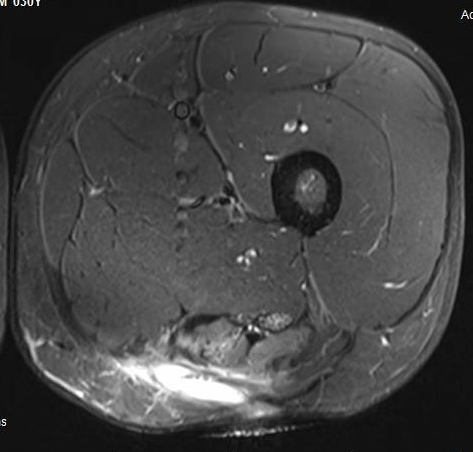

MRI

Proximal hamstring avulsion, with tendon floating in hematoma / seroma

Incomplete tears

High grade partial tear proximal hamstring

High grade partial tear proximal hamstring